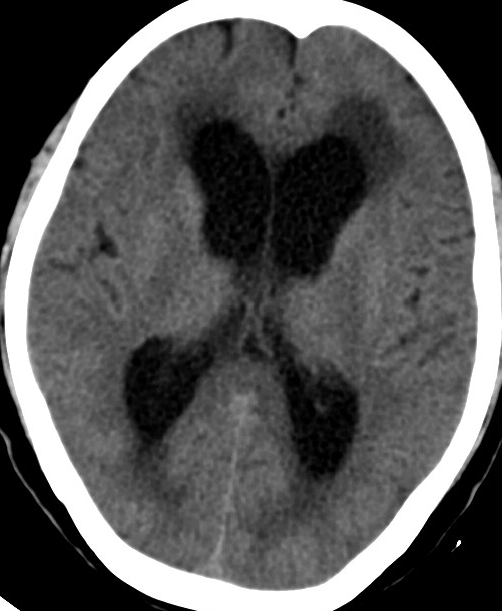

2013-8-8 CT

2013-8-7 脑室腹腔分流术,初压130

2013-8-8 仍诉头痛

2013-8-10 腰穿测压150mmH2O

2013-8-12 CT